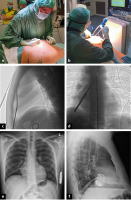

Abbildung 1: (a): Blunt Finger Dissection; (b–d): Schrittweise Tunnelierung unter lateraler Fluoroskopie – Bestätigung der Orientierung in ap; (e, f): Thoraxröntgen ap + seitlich